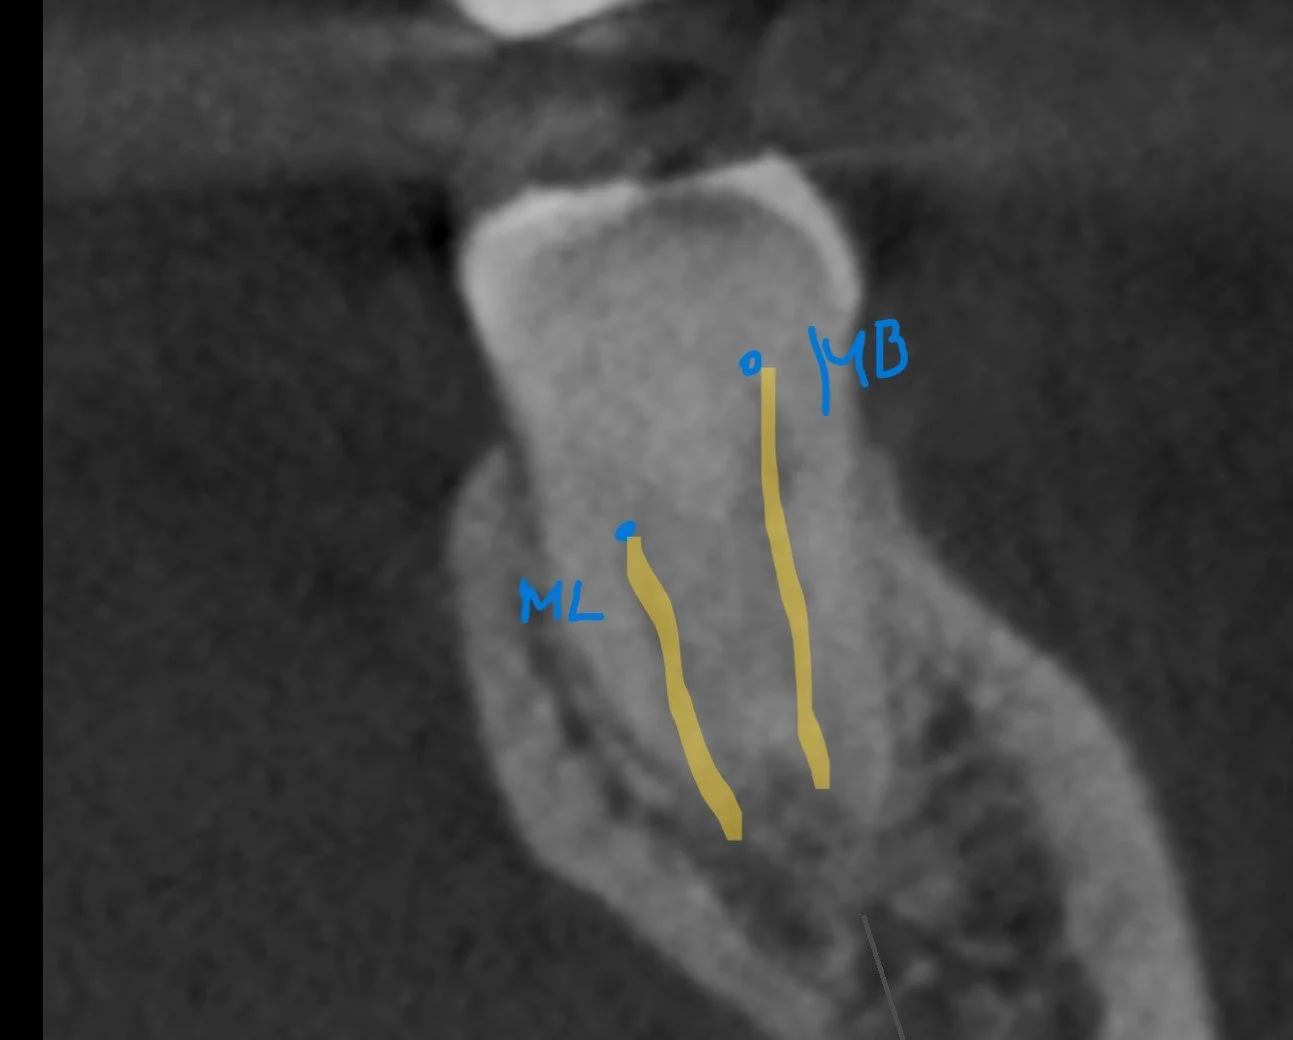

However the CBCT slices show heavy calcification of mesial buccal canal in coronal 1/3. The orifice to ML canal is likely to be buried underneath 3-4mm of tertiary dentine.

Coronal CBCT slice shows ML orifice likely to appears 3-4mm apical to floor of pulp chamber.